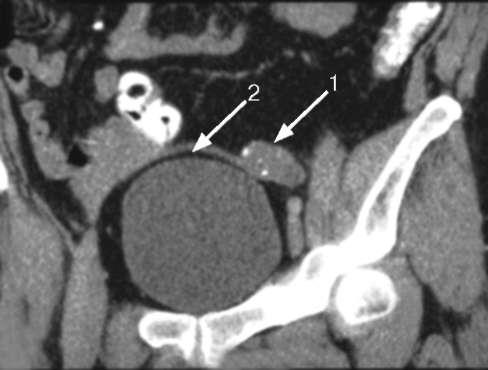

Крипторхизм. Это наиболее часто встречающаяся аномалия яичек. При этом пороке развития одно или оба яичка не спускаются в мошонку во время внутриутробного развития ребенка. Яичко задерживается в брюшной полости или на уровне пахового канала. Частота этой аномалии развития от 1 до 5% среди всех новорожденных мальчиков. У 10-15% детей с крипторхизмом, особенно недоношенных, яичко опускается в мошонку на протяжении первого месяца жизни, на протяжении последующих 6 месяцев еще у 30% детей яичко самостоятельно опускается в мошонку. Чаще всего, более чем в половине случаев встречается правосторонний крипторхизм, у 30% детей левосторонний, и у менее чем у 20% встречается двухстороннее неопущение яичек в мошонку. Крипторхизм бывает истинный и ложный.

При истинном крипторхизме яичко находится в паховой области выше наружного отверстия пахового канала или в брюшной полости. Обычно неопущенное яичко при истинном крипторхизме отстает в развитии, имеет меньшие размеры. Если яичко находится в брюшной полости, оно подвергается воздействию более высокой температуры тела (в брюшной полости температура выше, чем в мошонке на 2-3 градуса). В этом яичке возникают дегенеративные изменения, оно перестает выполнять свои функции. Если оба яичка находятся в брюшной полости у ребенка возникают эндокринные нарушения, связанные со снижением продукции яичками мужских половых гормонов. Мужские половые признаки развиваются недостаточно.

Диагноз крипторхизма устанавливают на основании осмотра, пальпации мошонки и пахового канала. Проводят радиоизотопное исследование, ультразвуковое и лапароскопическое исследования.

- УЗИ органов мошонки. Посредством ультразвукового исследования подтверждается отсутствие яичек, для их выявления при крипторхизме используют УЗИ брюшной полости, паховой области. Негативные результаты поиска или обнаружение дополнительных желез свидетельствует об аномалии их количества.

- КТ и МРТ органов таза. Компьютерную и магнитно-резонансную томографию применяют при неинформативности ультразвуковых исследований для подтверждения диагноза.